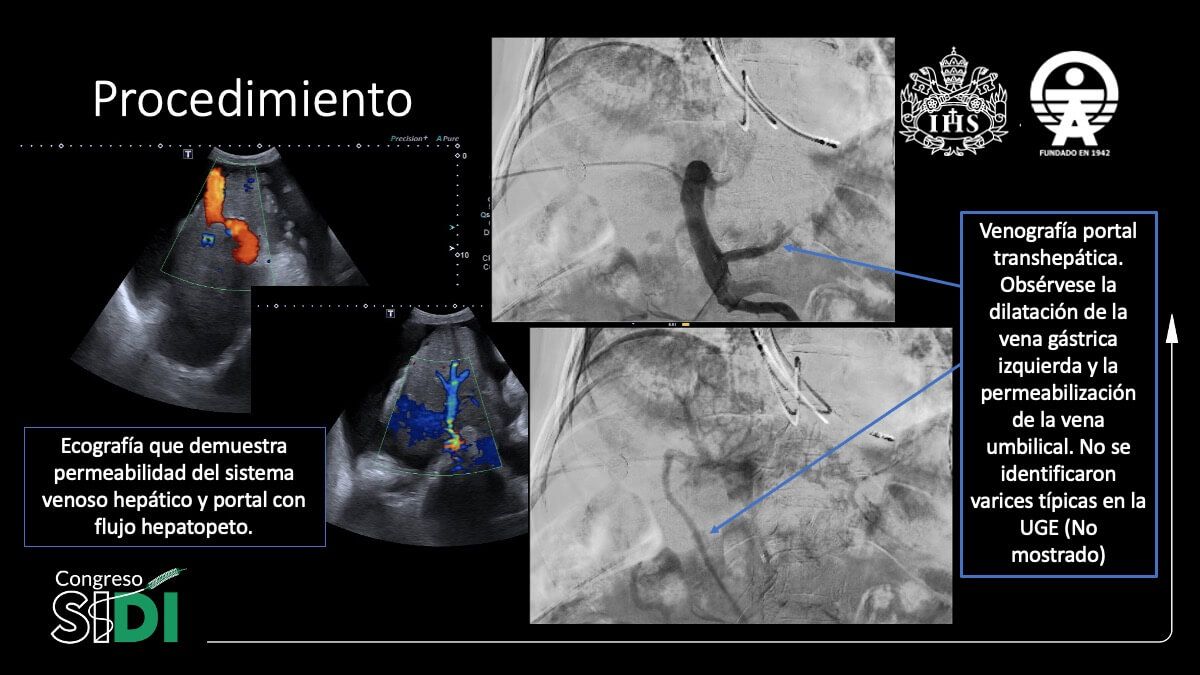

Hemorragia digestiva recurrente por varices ectópicas en paciente cirrótico: Experiencia exitosa en el abordaje intervencionista

Dr. Rommy Eduardo Olivieri